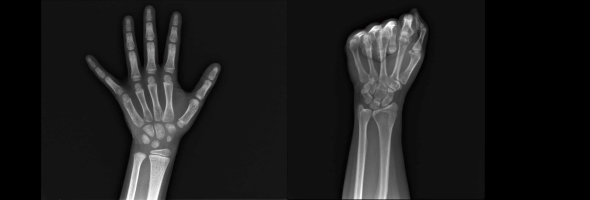

X射线骨龄仪 双能X射线骨龄骨密度仪 儿童骨龄AI评估软件

X射线骨龄仪

在儿童生长发育监测领域,骨龄评估是判断孩子生长潜力、预测成年身高的核心依据。然而,传统骨龄检测普遍存在两大痛点:人工读片误差大、报告解读耗时长,给家长和医生们带来困扰。安智龄智能AI骨龄仪以2秒极速成像、中华05/TW3双标准智能判读、一键生成报告等特点,重新定义儿童骨龄检测的精准性与便捷性,为儿科内分泌科、儿科及青少年运动选材提供高效解决方案。

骨骼健康是儿童生长发育的核心指标,而骨龄检测的准确性与安全性始终是家庭与医疗工作者关注的焦点。安智龄®X射线骨龄仪,专为儿童及青少年设计,集超低剂量辐射防护与超高清成像技术于一体,以科技赋能临床,让骨龄检测更安全、更清晰、更高效。